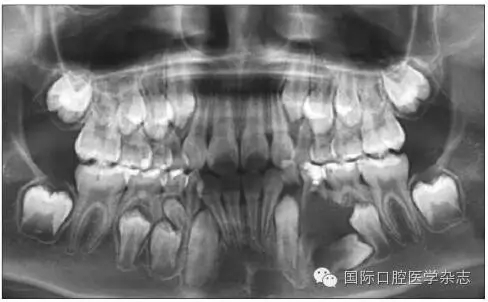

牙齒異位萌出是指恒牙在萌出過程中,未在牙列的正常位置萌出,兒童口腔臨床最常見的是上頜第一恒磨牙和上頜尖牙的異位萌出。造成第一恒磨牙異位萌出的原因包括:第二乳磨牙和第一恒磨牙的牙冠體積較大;頜骨的發(fā)育不足,尤其是上頜結(jié)節(jié)發(fā)育不足;第一恒磨牙的萌出角度異常,牙軸向近中傾斜等,歸根結(jié)底是在第一恒磨牙萌出階段出現(xiàn)了牙量和骨量不調(diào)的問題,頜骨發(fā)育不足是最主要的原因。發(fā)生率為2%~6%,男性多于女性,其中2/3發(fā)生在上頜,可單側(cè)或雙側(cè)對稱出現(xiàn)。第一恒磨牙的異位萌出常常造成第二乳磨牙早失,牙弓長度減小。臨床上,常用分牙簧分離第一恒磨牙與第二乳磨牙,或使用恒磨牙面粘著舌扣的Halterman矯治器,或變異Nance弓推第一恒磨牙向遠中的方法,改變恒牙萌出道,阻斷恒磨牙對乳磨牙的壓迫吸收,引導(dǎo)恒磨牙正常萌出。圖7顯示為一左上第一恒磨牙異位萌出的患兒,左上第二乳磨牙松動,牙弓長度減少[6]。

640.webp (6).jpg

左:口內(nèi)照;右:全景片。

圖7 左上第一恒磨牙異位萌出,左上第二乳磨牙松動

Fig 7 Ectopic eruption ofleft upper the first permanent molar, loose of left upper the second primarymolar